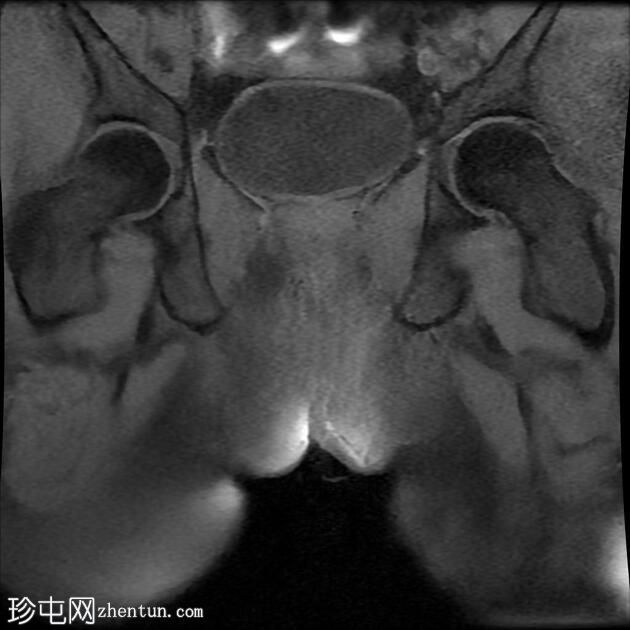

MRI

轴向位T2

脂肪饱和度

冠状位T1

一条68毫米厚的强化通道始于左侧肛周区域,向上穿过肛门内外括约肌,在2点钟方向开口于肛管。

无脓肿形成。

MRI成像特征与所述左侧经括约肌肛周瘘相符。